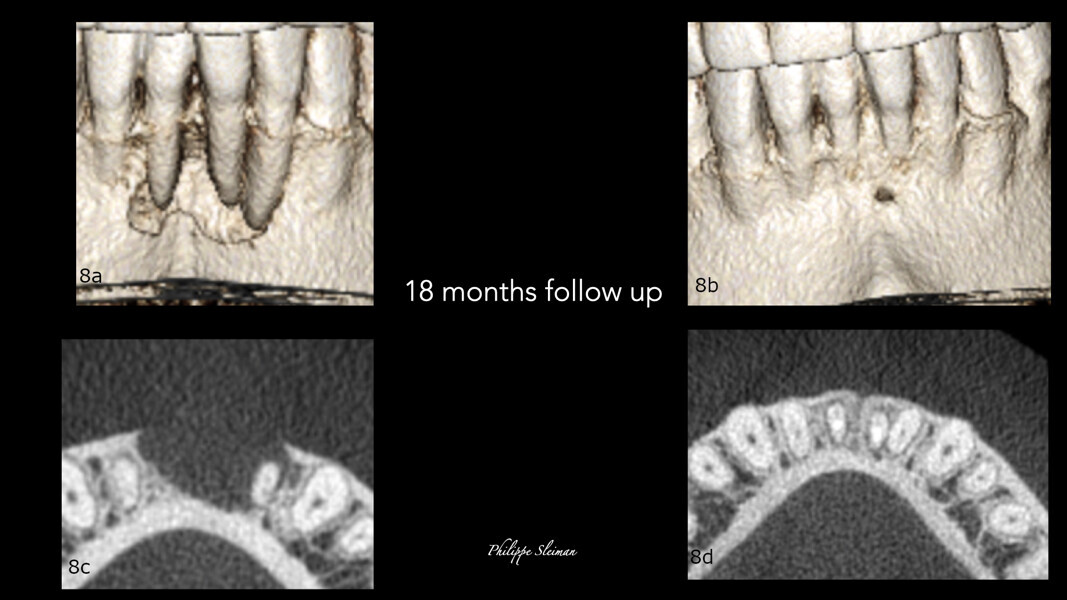

A comparison of the i-CAT scans taken preoperatively and at the nine-month and 18 month follow-ups showed complete regeneration of the cortical and trabecular bone in great biological detail, showing even the groove of the frenum (Figs. 7 & 8). The bone view clearly showed the preoperative major horizontal and vertical bone defect and open periodontal defect, the beautifully regenerated, natural looking bone and the emergence of the mandibular nerve. Happily, the bone continued growing vertically (Fig. 9).

Figs. 8a–d: Comparison of the bone and horizontal views of the pre-op (a & b) and 18-month follow-up i-CAT scans (c & d) regarding the bone healing and the closure of the pocket.